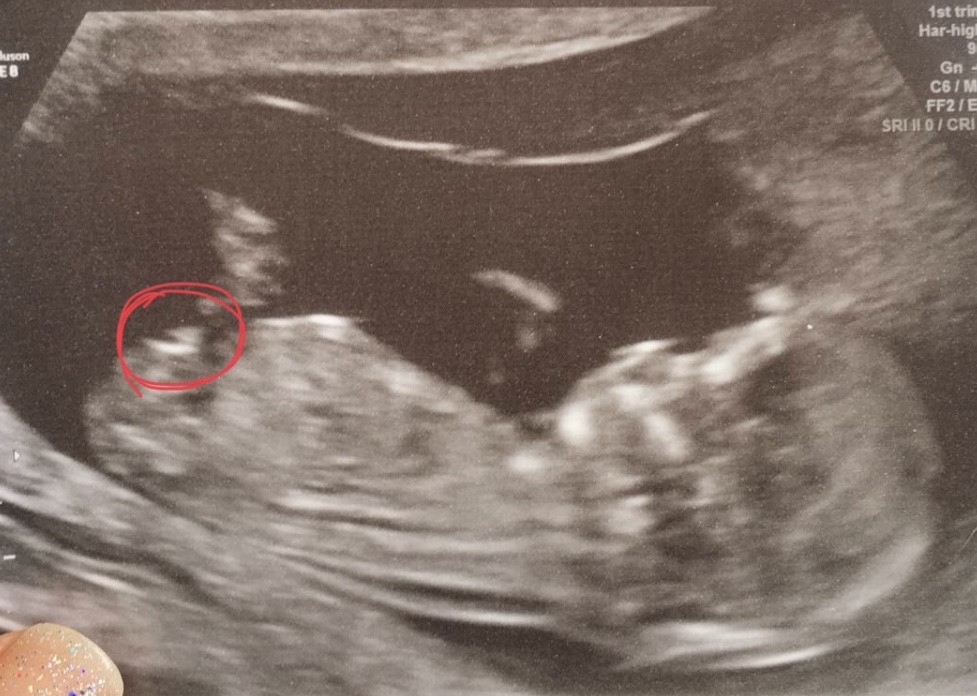

Attachment 39668Attachment 39669 Many thanks :)

I'm sorry, I don't feel like we're seeing the whole thing there. Adorable baby!